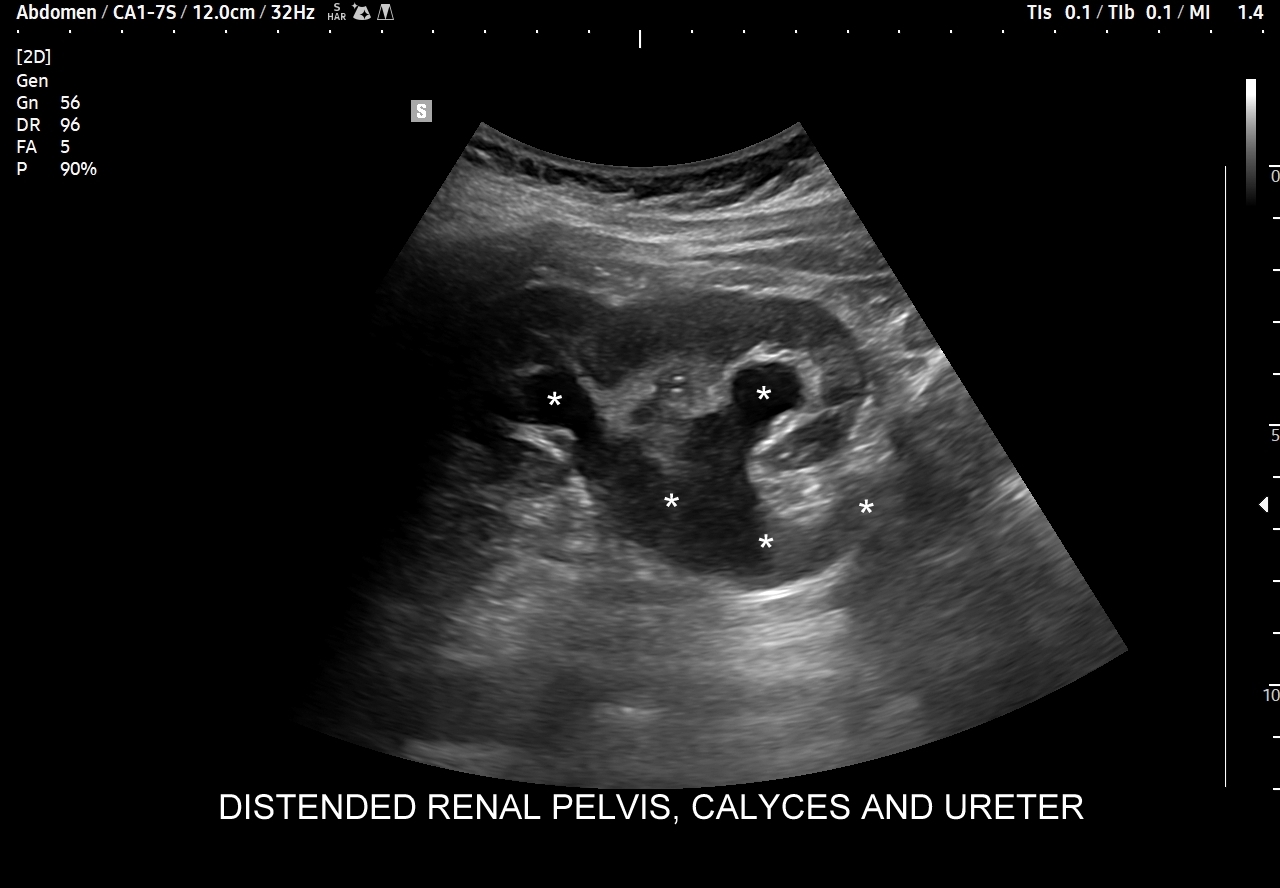

W badaniu USG ogniska endometriozy zwykle przyjmują formę hypoechogennych guzków i nieregularnych mas; mogą być niejednorodne echogenicznie i zawierać drobne obszary torbielowate; w trybie color-Doppler i MVI wykazują skąpe unaczynienie.

Na skanach w niniejszym artykule zaprezentowany jest przypadek endometriozy głębokiej w miednicy mniejszej z intraluminalnym nacieczeniem dystalnego odcinka moczowodu, jego całkowitą niedrożnością i wtórnym wodonerczem. Choroba w tak zaawansowanym stadium wykryta została przypadkowo w rutynowym przezbrzusznym badaniu USG jamy brzusznej. W ramach diagnostyki różnicowej przeprowadzone zostały badanie CT, MRI oraz ureterocystoskopia z pobraniem materiału do badania histopatologicznego, na podstawie którego postawiono rozpoznanie endometriozy.